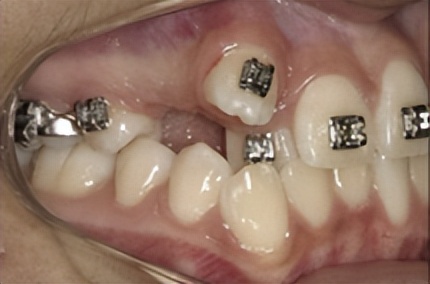

随着牙齿移动、拔牙间隙完全关闭

根据模型测量和X线影像分析结果,如果牙列拥挤严重或前突,则需要拔牙间隙更多的用于前牙往后移动;如果后牙咬合关系不佳,则通过后牙更多地向前移动来调整。

正畸医生通过矫治器的作用有效控制牙齿移动,最终将拔牙间隙完全关闭,因此是不需要镶牙的。

科学正确的拔牙矫正不会影响健康,相反,拔牙矫正可以将错位的牙齿排齐,牙齿直立于牙槽骨,有利于牙齿的健康,矫治后尖窝交错的咬合能够提高咀嚼效率。